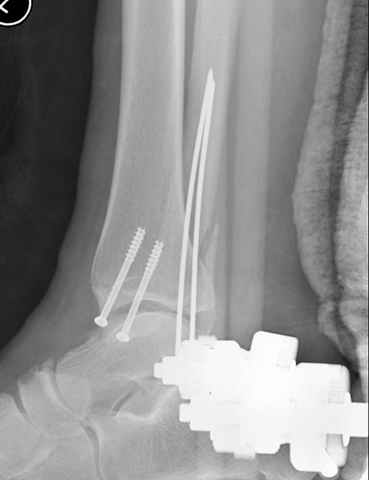

Pilon fracture:

конец малоберцевой кости, к нему прикрепляется латеральный суставной фрагмент дистального эпиметафиза большеберцовой кости (как на снимке)

и таранная кость, которые при репозиции малоберцовой кости репонируются автоматически.

За последнее 10-12 лет после стабилизации малоберцовой кости, стали применять более усовершенный, сложный, хорошо вам известный метод

Илизарова (кстати наряду с тибиал плато, пилон является одним из показанием по применению аппарата Илизарова при травмах) или Hybrid

Fixator, из минимальных доступов комбинированный метод для восстановления суставной поверхности-фиксация каннулированными

шурупами, создания жесткой системы фиксации до сращения перелома, защита от вальгусной деформации и на место образовавщегося метафизарного дефекта- костная пластика ауто костью или его

синтетические заменители, это сегодняшная тактика лечения.